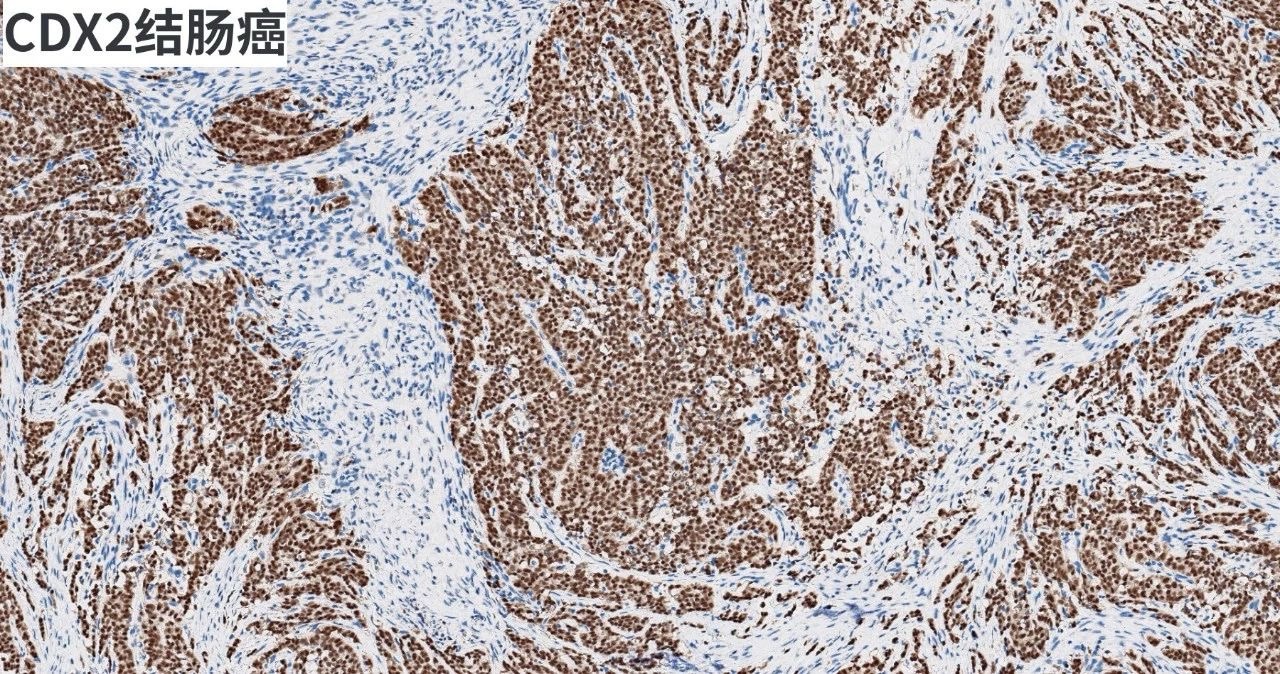

產(chǎn)品染色圖賞析